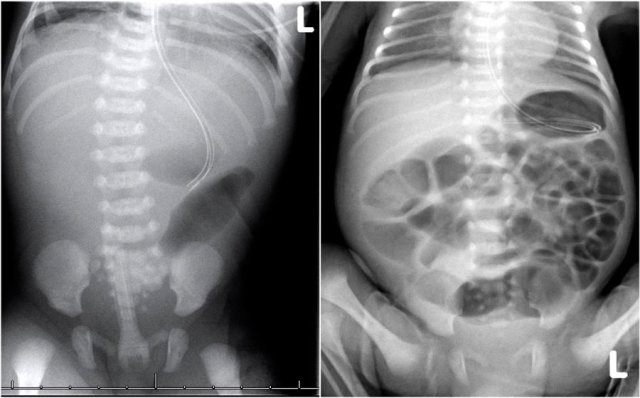

The left image shows a case of jejunal atresia.

More than three dilated loops indicate a low obstruction.

The image on the right is a case of ileal atresia.

The image shows a neonate with dilated bowel loops.

There is no air in the rectum.

This patient had a meconium ileus.